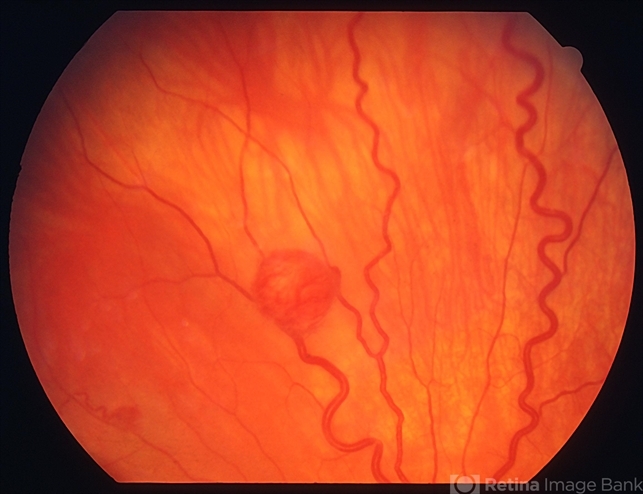

- Von Hippel Lindau disease

- Von Hippel-Lindau, retinal capillary hemangioma, hemangioma

- Retinal capillary haemangiomas, left superior periphery, in a 20 year old female with von Hippel-Lindau disease.